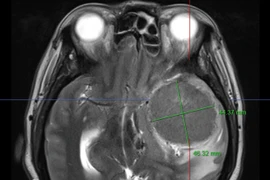

Đi khám đau đầu, phát hiện có u màng não "khủng": Bác sĩ cảnh báo gì?

Đau đầu, mệt mỏi triền miên, uống thuốc không đỡ, người phụ nữ 68 tuổi (TP HCM) đi khám tại bệnh viện Trưng Vương bất ngờ phát hiện có khối u màng não to hơn quả trứng vịt.